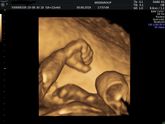

Всем привет! Была вчера на плановом приёме, по месячным срок 33,3 недель был, все у нас, Слава Богу, хорошо! Воды, плацента, кровотоки в норме! Головное предлежание.

НО… Вес ребенка 2760г! По УЗИ он на 35,5 недель. Но доктор сказал, что вообще не факт, … Читать далее